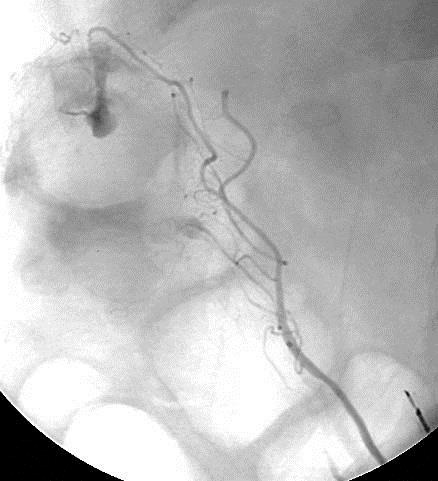

例外的情况 不能够发现肠系膜血管,特别是肠系膜下动脉,可以考虑肾下腹主动脉右前斜位造影